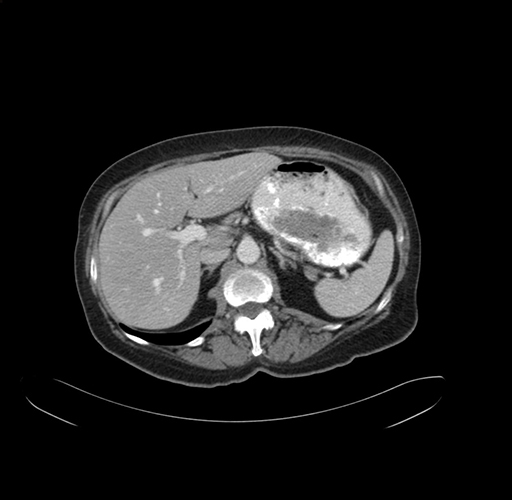

Pre-Chemo: Axial Venous